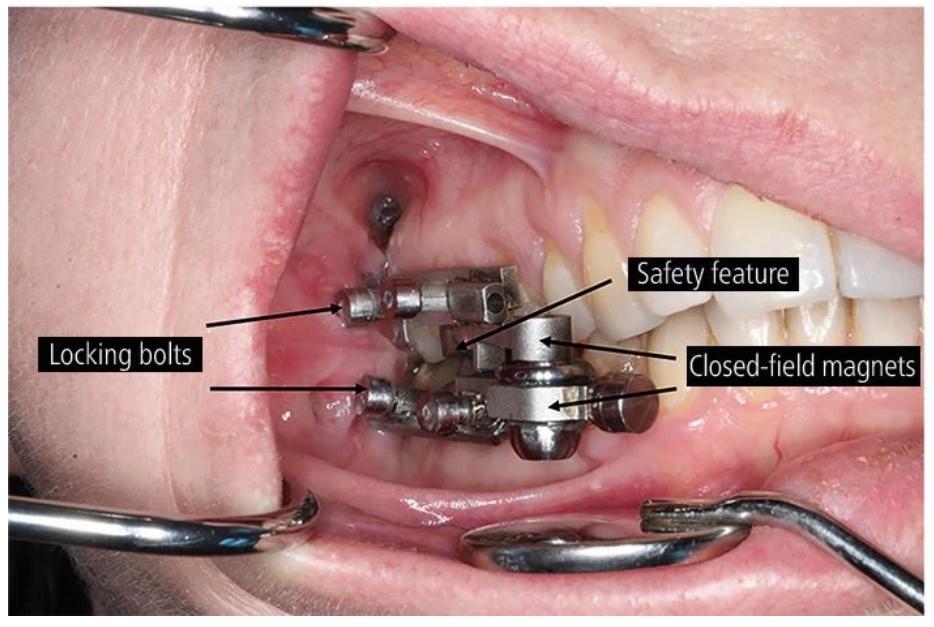

�� 猜猜看,它装在牙齿里长什么样?��

猜猜看,它装在牙齿里长什么样?�� 就是这么简单粗暴!

就是这么简单粗暴!这个装置名为Dental Slim Diet Control,看上去十分小巧,机器原理也很“简单粗暴”,通过安装在后排磨牙顶部和底部的磁性结构来限制使用者张开嘴巴的宽度,使其张嘴不超过2毫米——大概能塞下一根吸管的空间。奥塔哥大学研究人员称,这个装置可以有效地限制了参与者的流质饮食,同时不限制呼吸和言论自由。

装在真人牙齿里看起来是这样的

装在真人牙齿里看起来是这样的Dental Slim一经推出,在社交媒体上引发热议,不少网友感到难以理解甚至愤怒,有人说“我们这些胖子根本管不住嘴”。